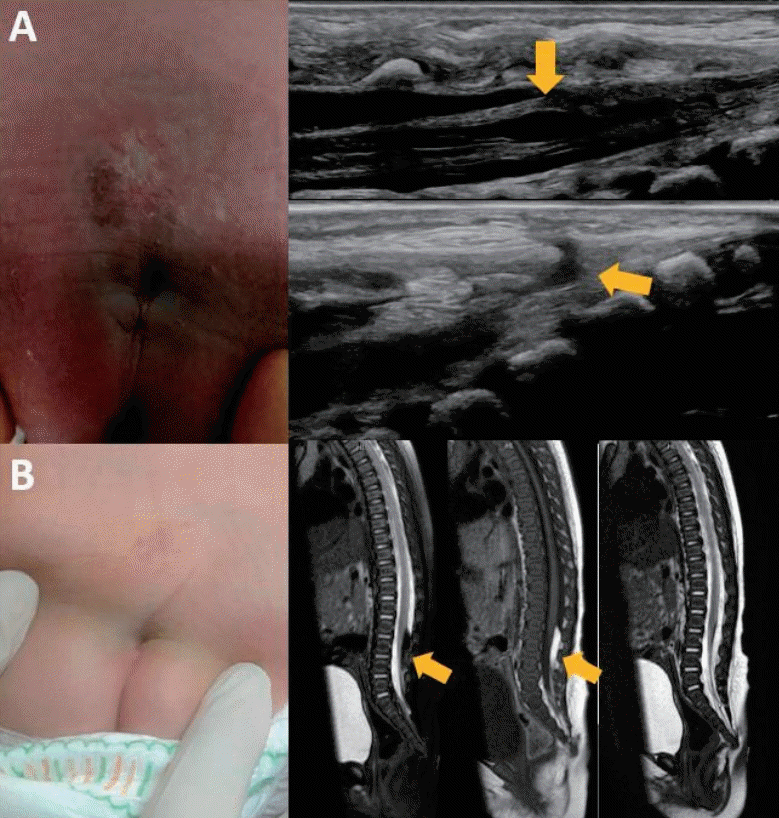

A stepwise diagnostic approach to suspected spinal dysraphism should be guided by evidence-based criteria to determine the need for imaging. Spinal ultrasonography is widely recommended as the initial screening modality for infants with atypical sacral dimples, particularly those younger than 4–6 months of age, before ossification of the posterior elements limits acoustic windows [5]. It is favored as an initial tool because of its high sensitivity and specificity (both approximately 96%) as well as its safety and cost-effectiveness (Fig. 4A) [5,23,24]. Nevertheless, recent evidence indicates that a routine ultrasonographic screening may not be necessary in cases of isolated, simple sacral dimples that lack high-risk cutaneous markers [3,21,23]. The feasibility of spinal ultrasonography in neonates is attributed to incomplete ossification of the posterior vertebral arch, a normal feature of infancy, and the osseous defects seen in spina bifida, both of which allow sound wave penetration and adequate visualization of the spinal canal [25].

Imaging findings of lipomyelomeningocele in 2 patients. (A) Spinal ultrasonography image showing a fistulous tract extending from the skin’s surface to the spinal canal (bottom arrow). The conus medullaris is tethered and extends down to the sacral level. A focal cystic lesion is observed at the L5–S1 level (top arrow). (B) Preoperative sagittal T1-weighted magnetic resonance image showing a high-signal-intensity mass located dorsally within the intradural space at the L2–4 levels. The conus medullaris is lowlying with a cord-like fat signal extending along the filum terminale (arrow). No significant vertebral defect or dural ectasia is visible. Postoperative imaging (far right) shows resolution of the intradural mass.

For patients with fewer than 2 of the following—cutaneous stigmata, atypical dimples, or gluteal cleft deviation—lumbar ultrasonography during the first month of life is advised, with subsequent magnetic resonance imaging (MRI) reserved for cases in which abnormalities are detected. Conversely, in infants presenting with a neurological or orthopedic impairment, multiple cutaneous stigmata, or specific high-risk markers such as dermal sinus, a human tail, or subcutaneous lipoma, MRI should be performed directly given the elevated risk of spinal dysraphism [3]. When an additional evaluation is warranted, MRI offers superior anatomical detail, particularly for assessing the level of the conus medullaris; the thickness and morphology of the filum terminale; tethering lesions; and associated bony dysraphic anomalies [26]. Prone MRI can be considered in select cases, such as patients with prior tethered cord release or high clinical suspicion despite normal findings on supine MRI. However, prone imaging offers limited additional diagnostic value if abnormalities are already evident in standard supine MRI studies [27]. MRI in infants and young children often requires sedation; beyond the risk of sedation failure, complications such as bradycardia and hypotension reportedly occur in 3%–8% of cases, underscoring the need for careful consideration when performing the examination [28,29].

The imaging findings of conditions that may be associated with a sacral dimple are as follows (Table 3). Lipomyelomeningocele typically presents as subcutaneous fat tethering the cord that poses a risk for tethered cord syndrome. T1-weighted MRI shows fat signals that are otherwise suppressed on fat-saturated sequences, with a low-lying conus and a deformed, tethered neural placode. Although lipomyelomeningocele is rare, its early recognition is crucial to preventing neurological deterioration (Fig. 4B) [33]. Dermal sinus tracts are epithelial-lined tracts that may extend to the spinal cord and carry a significant risk of infection, including meningitis. A tethered cord is present in approximately 62.5% of cases and often accompanied by a thickened filum, and the tract may be directly visualized on MRI [34]. Conus lipomas are frequently encountered and often tether the cord, with anatomical variations that can complicate their surgical management. They appear as T1 hyperintense masses in the low-lying conus and are sometimes associated with syringomyelia or sacral agenesis [35]. Similarly, filar lipomas are common findings, appearing as fat signals (>2 mm) within the filum terminale that can cause tethering or be incidental [36]. A tight filum terminale may impair normal ascent of the conus and is often associated with other spinal malformations. Imaging typically demonstrates a thickened filum (>2 mm) with a low-lying conus, while dynamic MRI can reveal restricted filar motion [37].